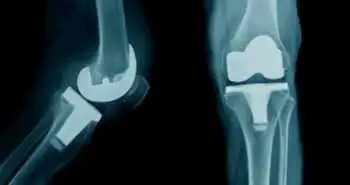

Внутрисуставное введение сприфермина (рекомбинантного фактора роста человеческих фибробластов 18) было признано безопасным у пациентов с деформирующим остеоартрозом (ДOA) коленного сустава, как показало исследование, результаты которого опубликованы в Arthritis Research & Therapy.